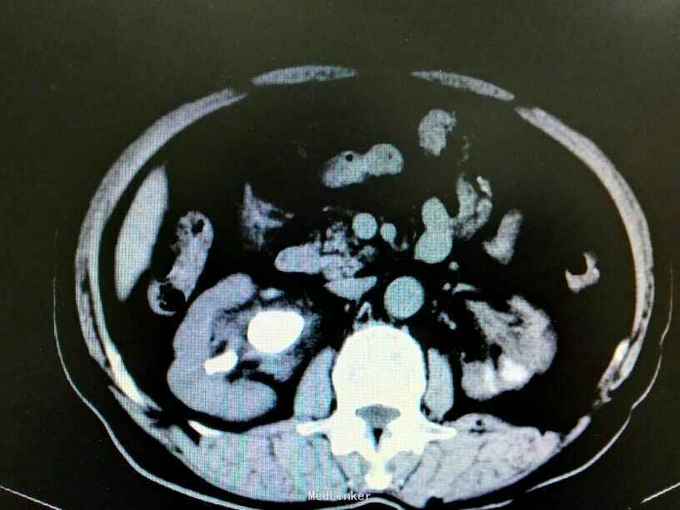

双肾铸型结石伴左肾萎缩一例

72岁男性,因“体检发现双肾结石1月”。既往10年前因双肾结石行双侧肾盂切开取石术(具体不详)。4年前因右肾输尿管结石行右侧输尿管碎石术。

双肾区叩痛。尿常规白细胞1500个/ul,两次尿培养阴性。左肾GFR15右侧38.9。

双肾铸型结石 左肾萎缩,尿路感染,双肾盂切开取石术后,BPH。经抗感染等治疗后,现在尿常规白细胞395.4个/ul。